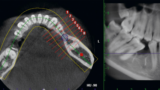

歯科での診断と治療内容(レントゲン・根管治療・切開など)

- レントゲン・CT撮影:根の感染や骨の状態を確認